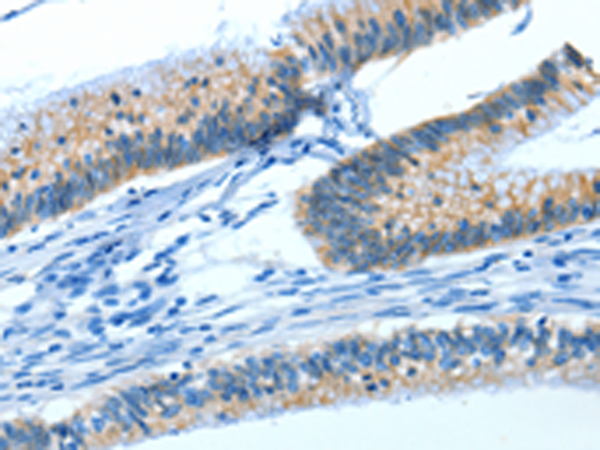

分类: 科研抗体货号: P04561别名:应用: IHC反应种属: Human, Mouse, Rat